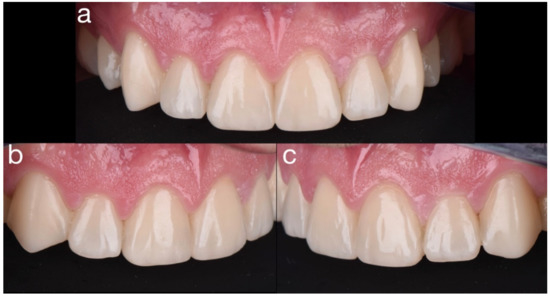

2.2. Restorative Phase